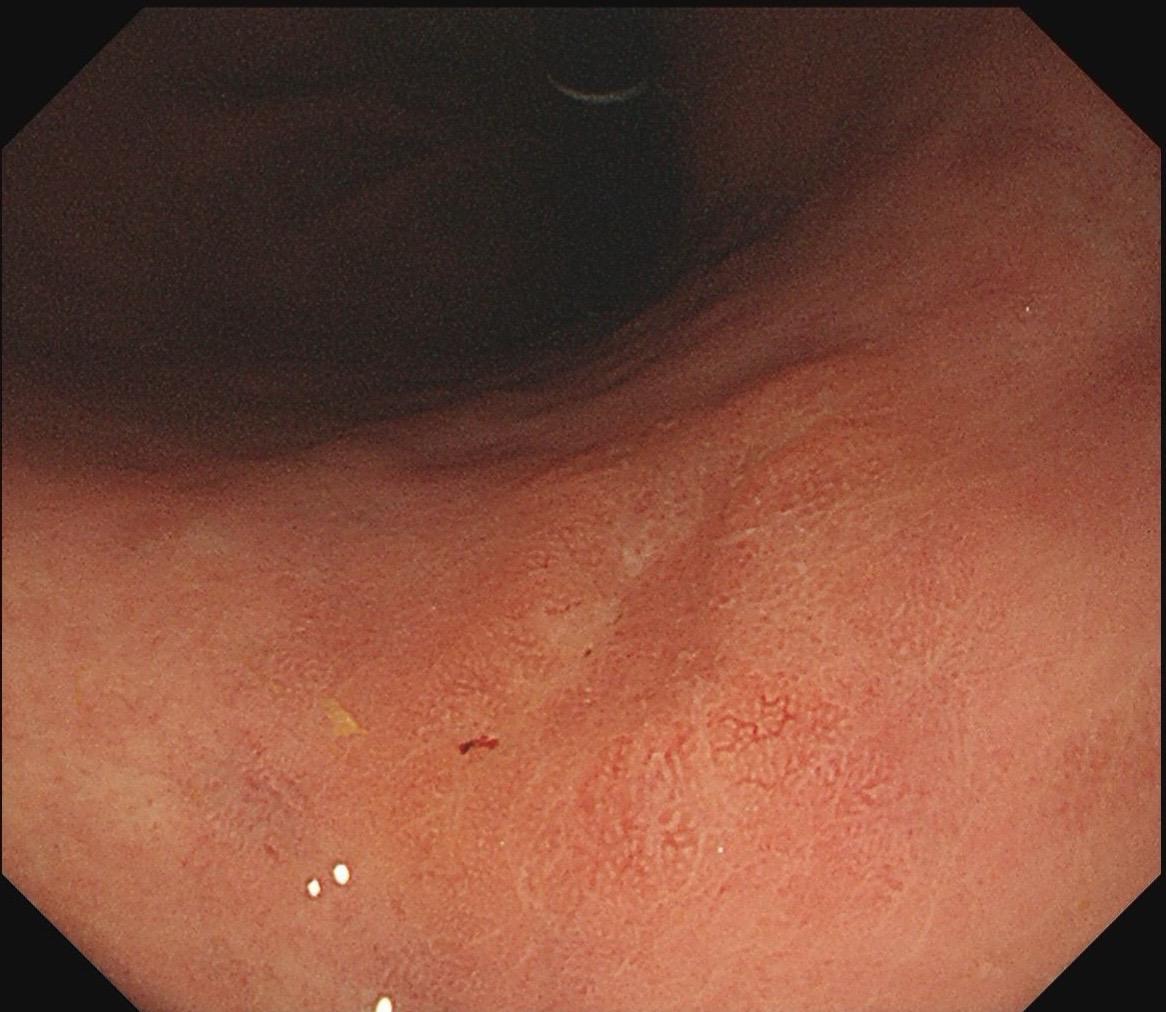

女,57岁,胃角。同事熟人,萎缩背景,色调淡黄,中央浅凹陷,腺管小而密集。